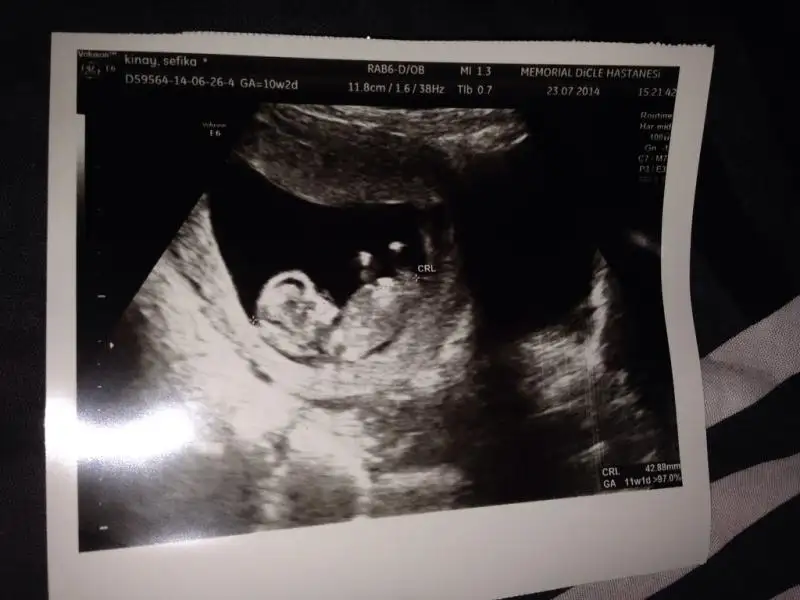

kızlar birde benim bebişime bakın bakalımmmm :) Dün doktora gittik 10+3 günlük 2 hafta sonra 2li test yapılcak ve doktor büyük ihtimal cinsiyeti belli olur dedi..Ama herkes gibi bende çok merak ediyorum tabi öncelikle beden ve zihin sağlığı ama insan hep merak eder ya :) yorumları bekliyorum şimdiden teşekkürlerrrr